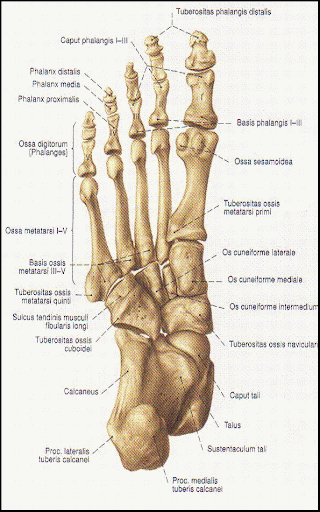

Os naviculare перевод

Os naviculare перевод 144 фотографий